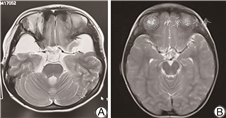

电话回访112例未同意复筛的患儿,其中拒接电话22例,接受电话回访的新生儿家长均回复婴儿生后至今(随访年龄0~3岁)健康。对8例确诊IEM患儿进行追踪随访及智力评估(随访年龄0~3岁),1例甲基丙二酸血症患儿早期头颅MRI显示双侧苍白球区、双侧尾状核头对称片状异常信号;1例戊二酸血症患儿早期头颅MRI提示额叶白质内等T1长T2信号,提示双侧额叶白质脱髓鞘。所有确诊病例均给予对应的治疗,包括特殊奶粉、补充左卡尼汀、维生素B12及尼替西农等,目前均生长发育良好。其中甲基丙二酸血症患儿随访至2岁、戊二酸血症患儿随访至2.5岁时头颅MRI均提示正常,智力正常。见图1、2。

本研究确诊甲基丙二酸血症1例,串联质谱筛查提示甲基丙二酸及丙酰肉碱明显增高,基因检测MUT基因c.729_730insTT(p.Asp244LeufsTer39)及c.424A>G(p.Thr142Ala)复合杂合变异,可能影响底物结合区和钴胺素结合区功能[10, 11],为致病变异。头颅MRI提示双侧额叶白质脱髓鞘,侧脑室轻度扩张,经维生素B12、左卡尼汀治疗,并予以饮食干预,临床症状消失,随访至2岁,韦氏量表测试智力正常,复查MRI正常。本研究确诊戊二酸血症Ⅰ型1例,该病可能导致大头畸形、肌张力异常及运动障碍等神经系统发育异常[12],该患儿血串联质谱提示戊二酰肉碱、戊二酰肉碱/辛酰肉碱水平升高,头颅MRI提示双侧颞部蛛网膜下腔明显扩大,基因检测及家系验证为GCDH基因c.1109T>C(p.L370P)及c.395G>A(p.R132Q)复合杂合变异,变异位点分别来源于父母,予口服维生素B2及左卡尼汀,随访到2岁半,复查头颅MRI正常,头围稍大,无神经系统发育障碍。